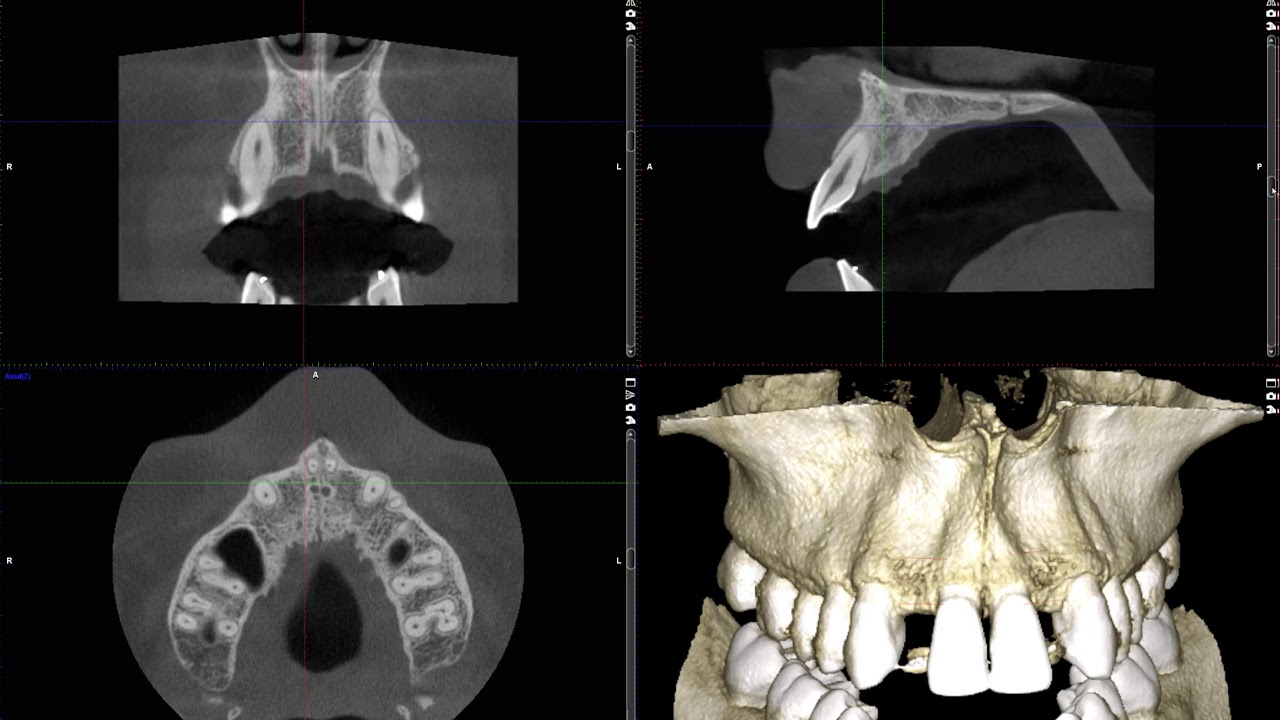

Implant planning for congenitally missing lateral incisors